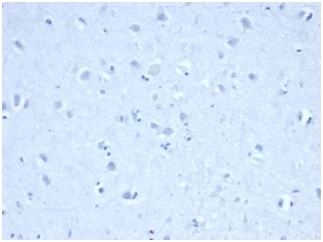

Negative control: IHC staining of FFPE human cerebellum tissue with IDH1 R132H antibody (clone IDH1/6806R) at 2ug/ml in PBS for 30min RT. HIER: boil tissue sections in pH 9 10mM Tris with 1mM EDTA for 20 min and allow to cool before testing.